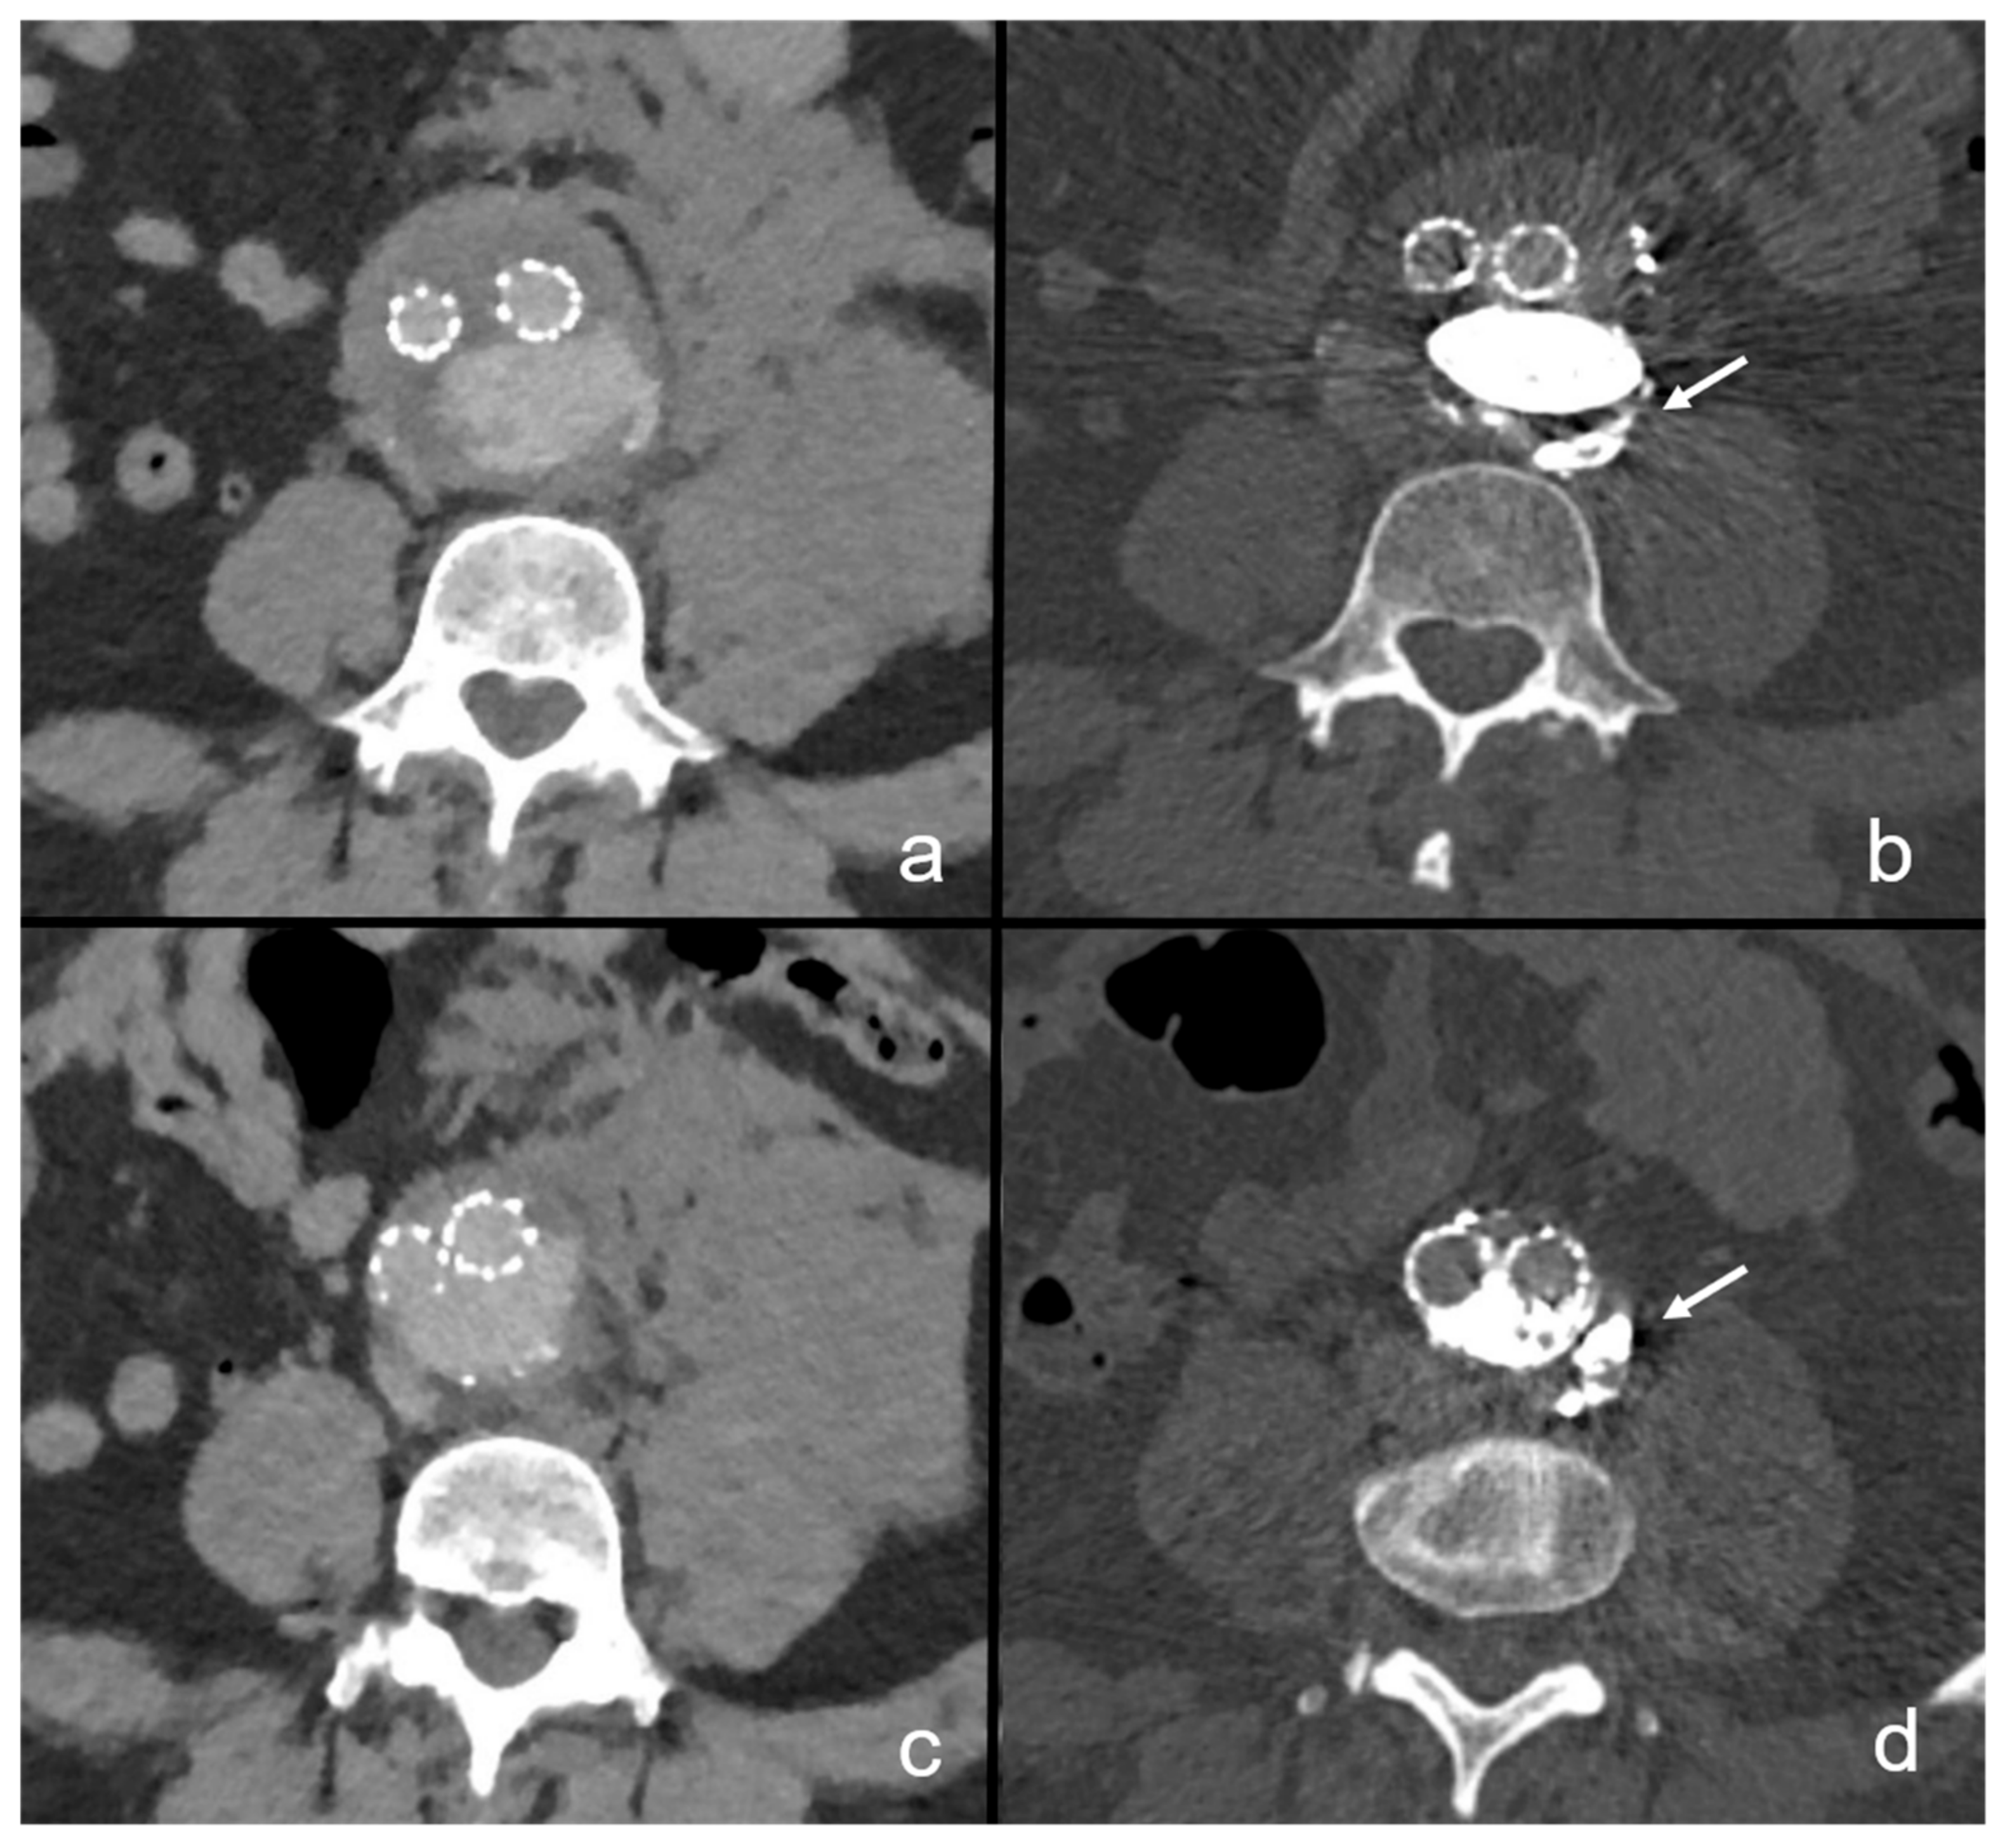

Figure 4.

Retroperitoneal extravasation of NBCA immediately after embolization. In this patient, aneurysm rupture occurred due to a type 1b endoleak after previous EVAR. Images (a,c) present the ruptured situs with extensive left-sided retroperitoneal hematoma, suggesting location of the rupture site at the left aneurysm wall. This patient underwent endovascular prosthesis revision with sac embolization and targeted embolization of the rupture site with NBCA. Three months after the procedure, small residual retroperitoneal extravasations adjacent to the left aortic wall can be delineated, proving the rupture site to be occluded (b,d).